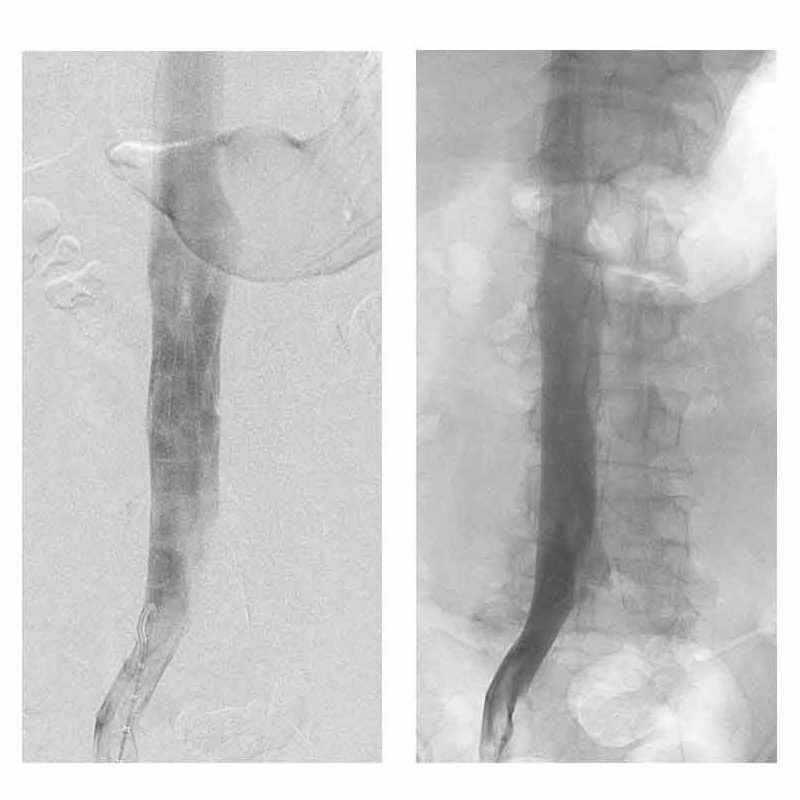

Femoral versus jugular access for Denali Vena Cava Filter placement